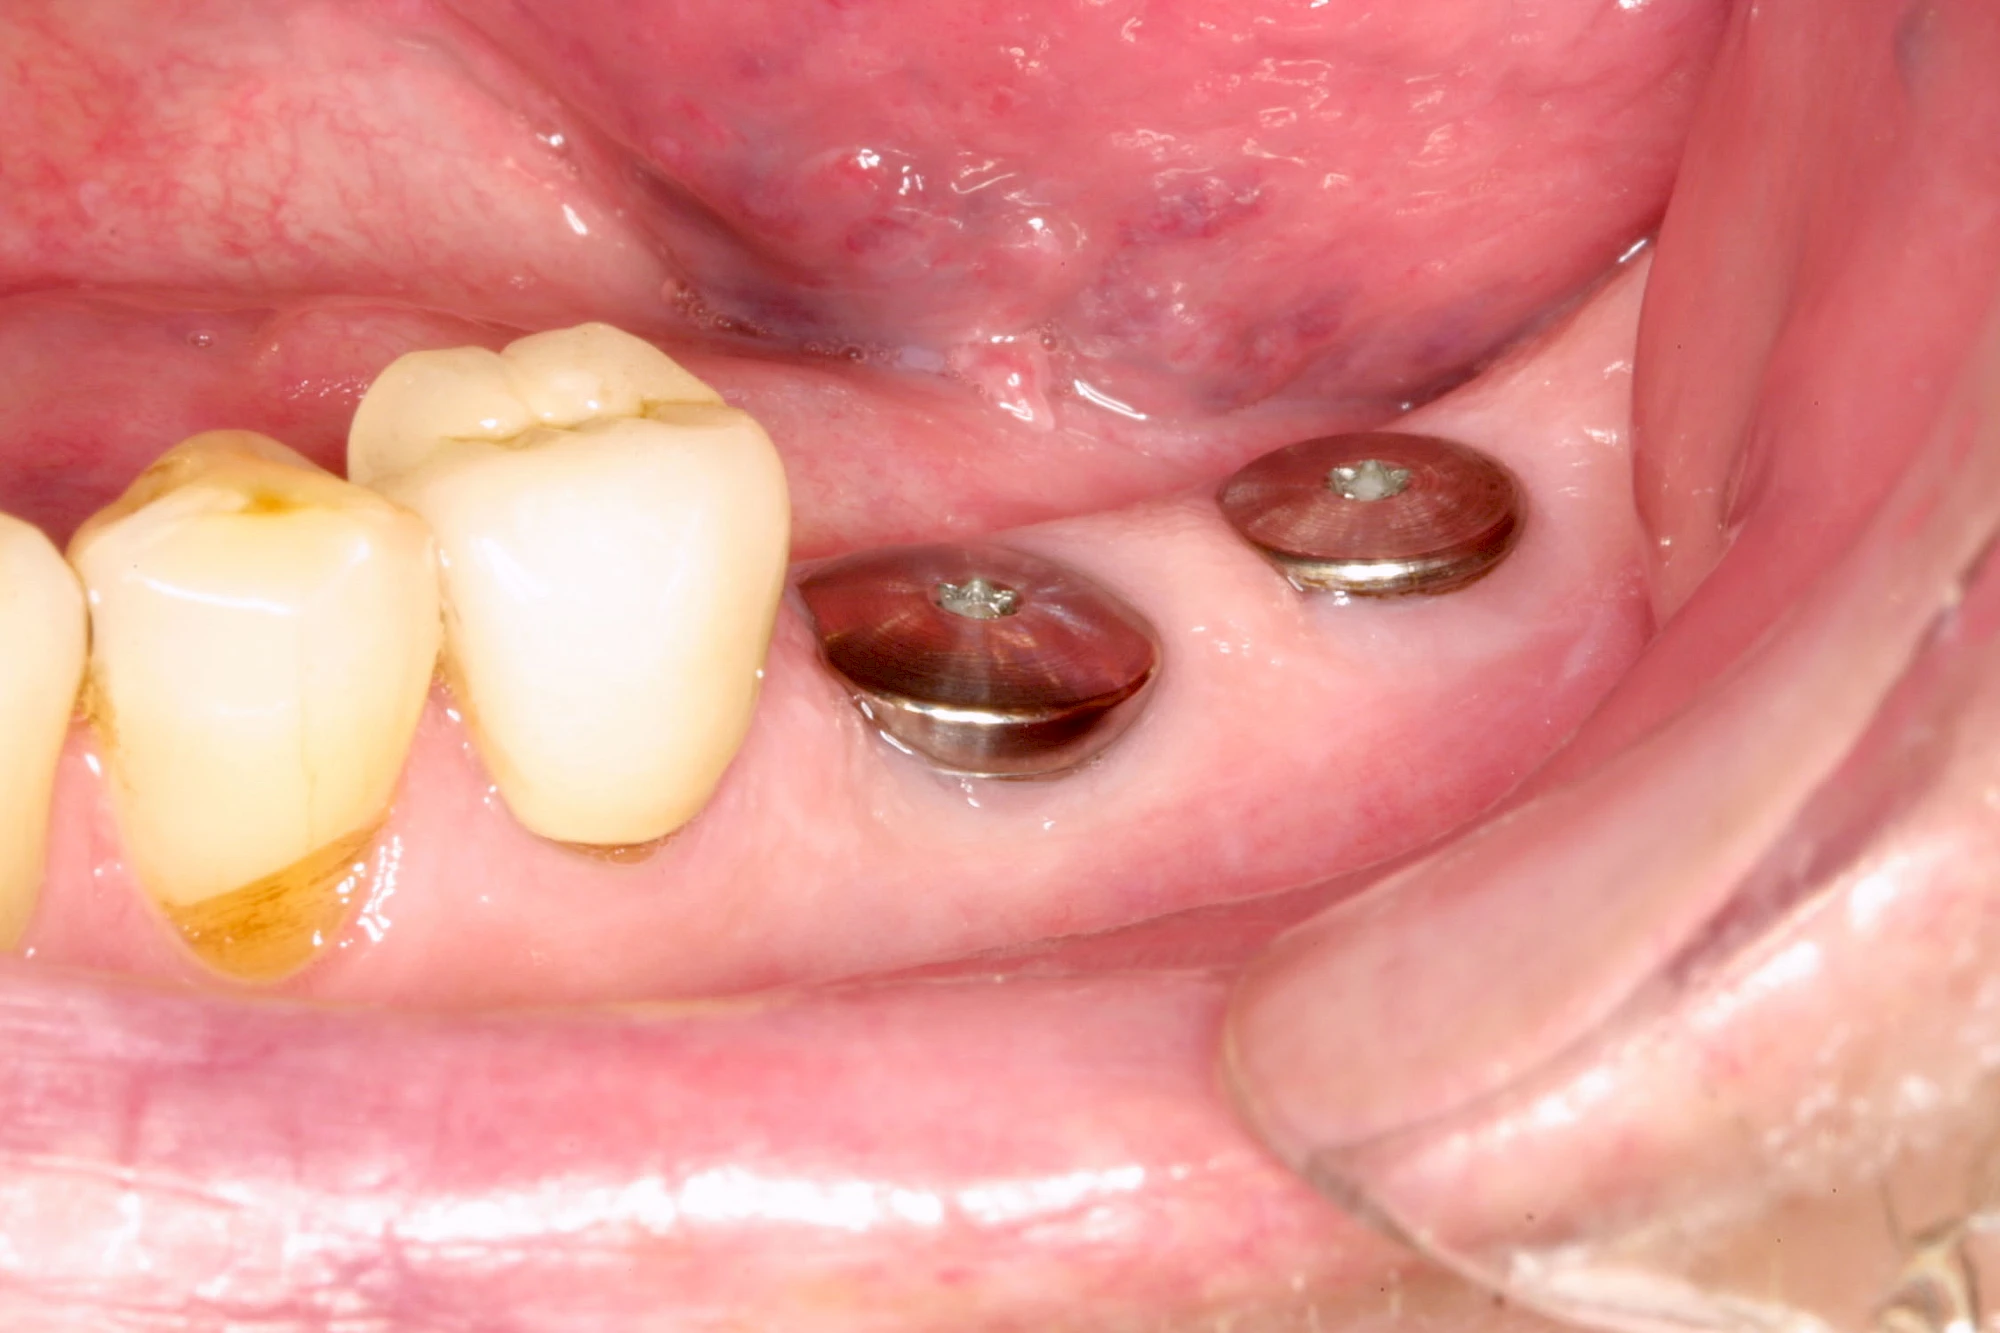

Implantate: Prothesen

Bei herausnehmbaren Prothesen werden Implantate eingesetzt, um den Halt und den Tragekomfort der Prothesen zu verbessern. Dazu kommen verschiedene Verbindungselemente zum Einsatz:

- Teleskope

- Kugelköpfe

- Tellerförmige Lokatoren

- Stege

- Magnete (selten)

Neben rein implantat-getragenen zahnärztlichen Versorgungen werden bei herausnehmbaren Prothesen Implantate auch in Sinne einer "strategischen Pfeilervermehrung" ergänzend zu eigenen Zähnen zur Verankerung eines Zahnersatzes genutzt.

Varianten zur Verankerung von abnehmbarem Zahnersatz auf Implantaten